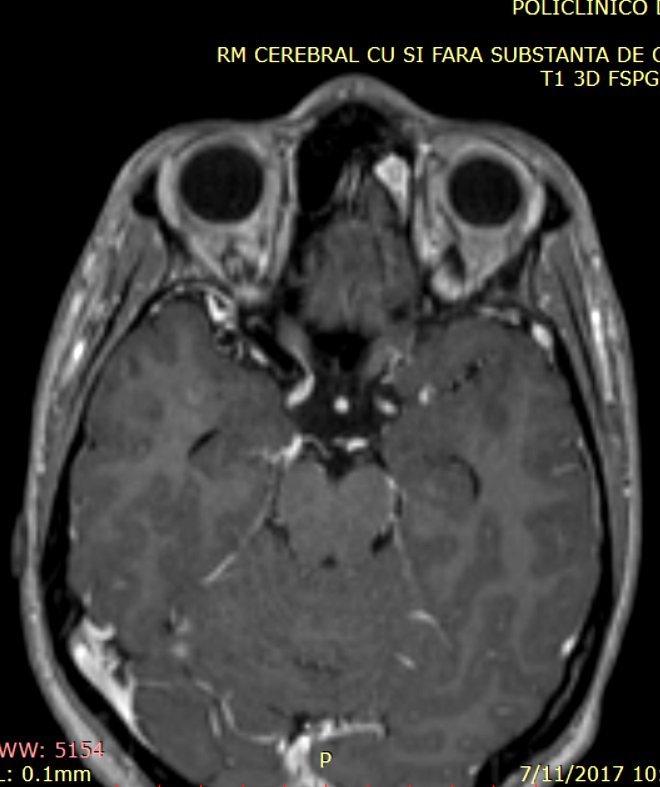

RMN cu substanţă de contrast efectuat postoperator confirmă existenţa unei restanțe tumorale cu un volum de aprox. 10% din volumul tumoral iniţial, situată în canalul nazofrontal stâng şi în sinusul frontal stâng (fig. 3).

Fig.3: RMN postoperator: restanta tumorala localizata in canalul nazofrontal stg